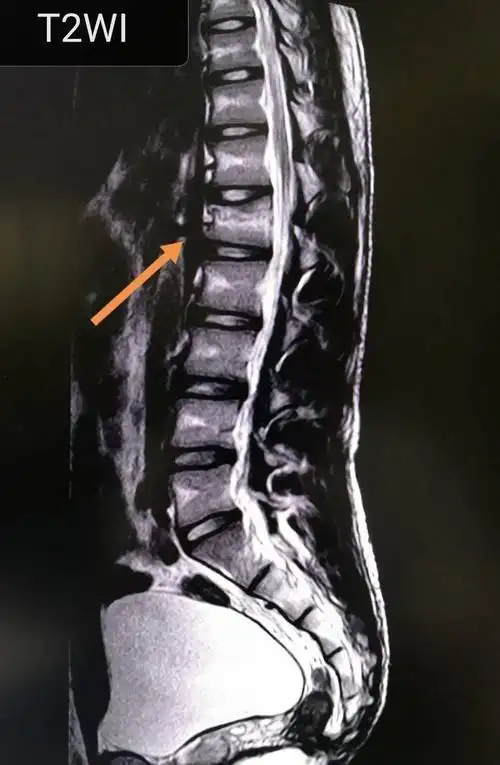

腰椎滑脱病理分析